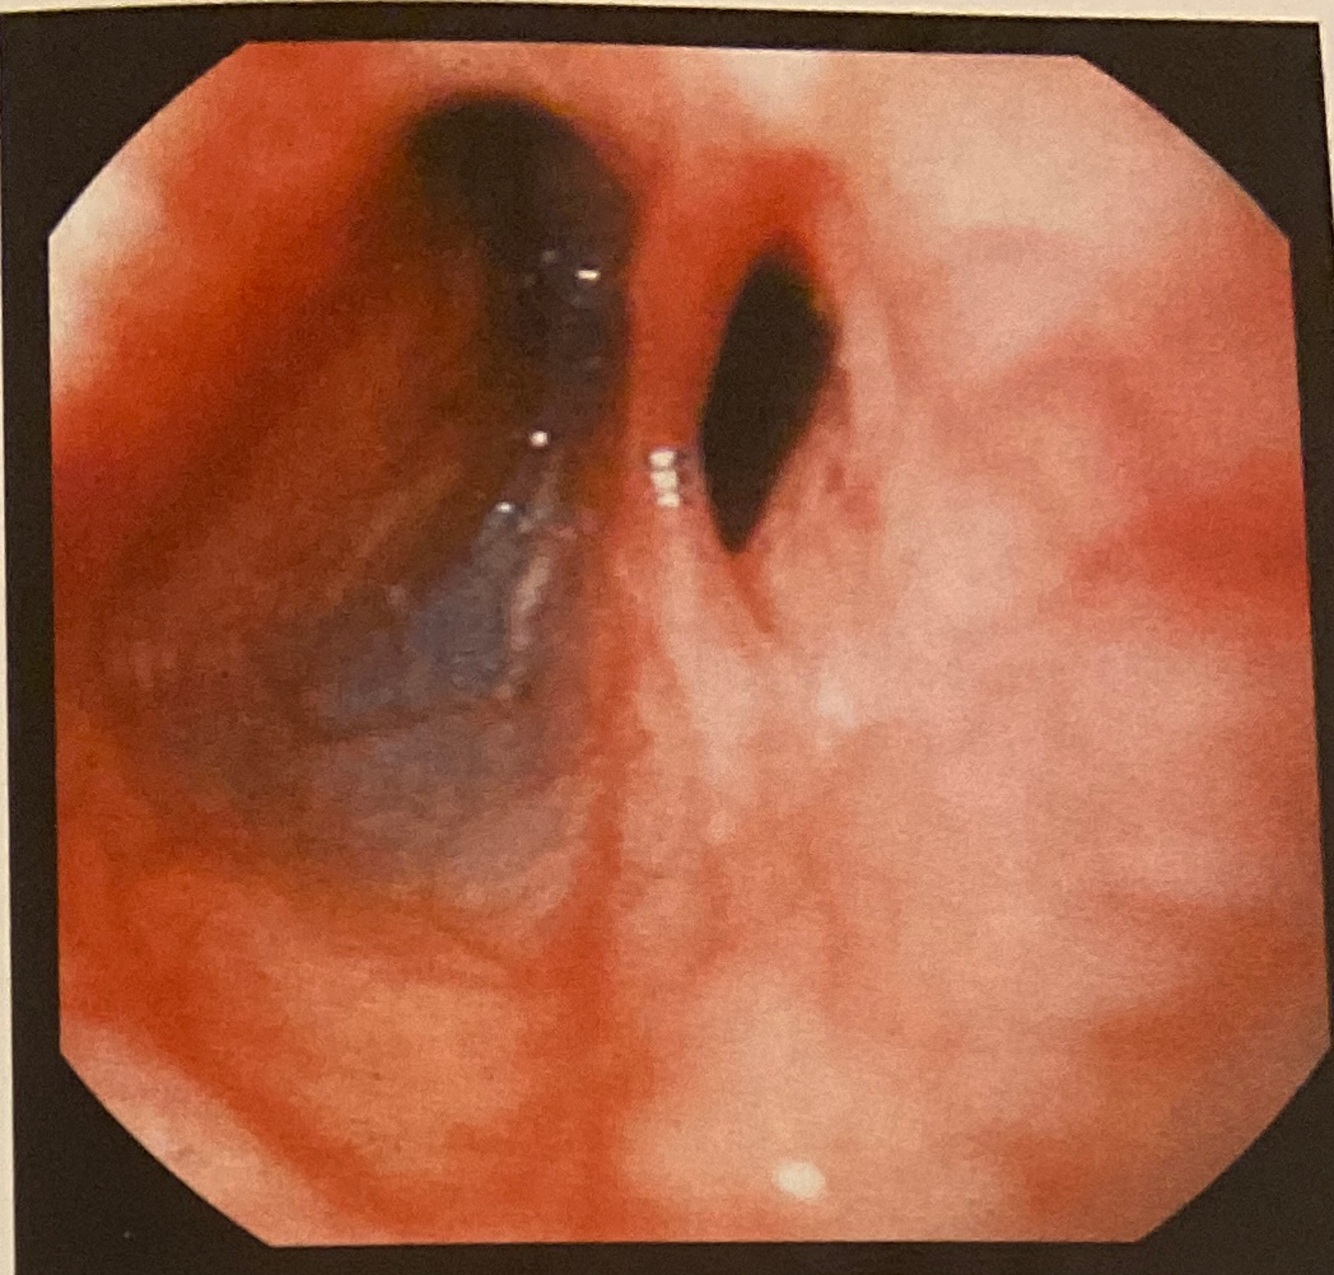

Esôfago

Câncer esofágico